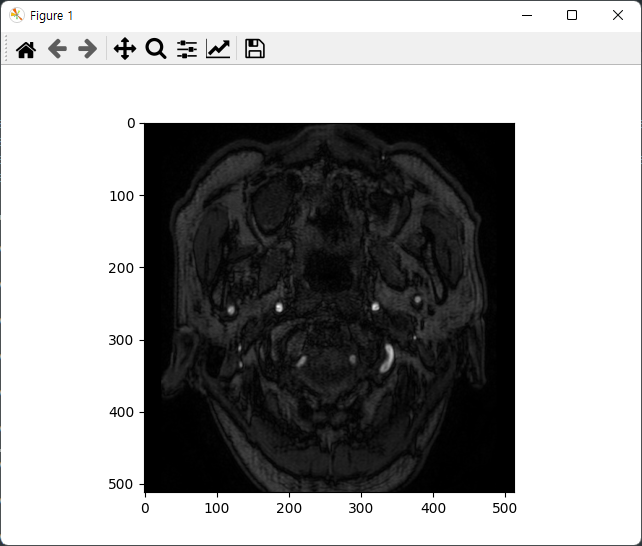

불러온 데이터를 저장한 객체인 data_slice 변수에 pixel_array에 접근하여 시각화를 진행해 보았습니다.

Matplot의 Imshow함수의 Color Map Default 값은 "viridis"이기 때문에 cmap를 설정하지 않고 시각화를 진행하면 왼쪽과 같은 이미지가 출력되는 것을 확인할 수 있습니다.

따라서 일반적으로 DICOM Viewer에서 보는 색감으로 보고 싶은 분께서는 cmap = 'gray'을 사용하시면 될 것 같습니다.